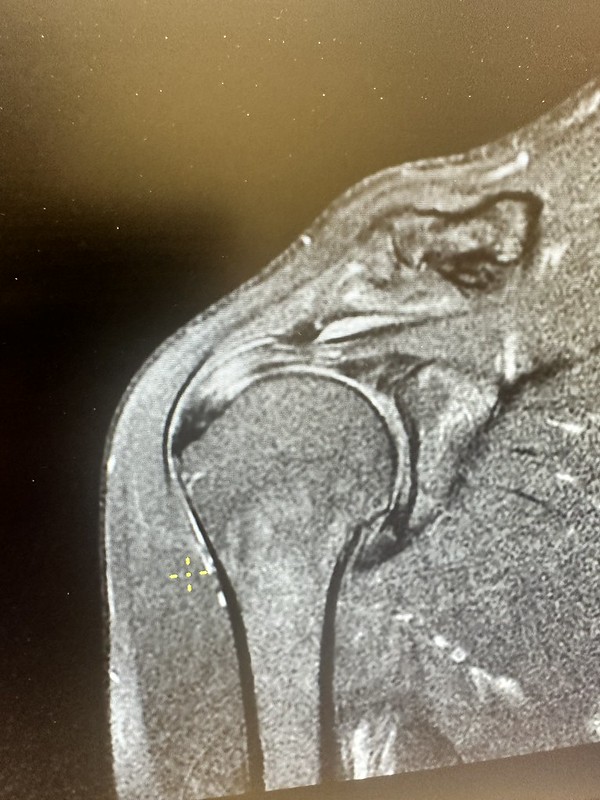

Above is the MRI I got in Uzbekistan. My doctor here in Michigan was impressed with the quality and said it was the same quality as Michigan hospitals. He was shocked that it cost me around $50. He diagnosed no major red flags requiring surgery. He pointed out inflammation in the tendon above the joint socket. On the MRI it was lighter in color on the left side. It is an impingement problem when the tissue is inflamed, it is trapped between two hard surfaces. He said I could get surgery and he would shave the bone spur and try to clean the socket and strengthen the tendons. However, he did not recommend this and gave me a cortisone shot and told me that I should be able to continue doing pushups, etc. I have a full range of motion, strength in the joint, and mild pain symptoms. He also indicated that research didn’t show much with sleep position and suggested perhaps it was a psycho-somatic mind trick. When I sleep on my side, I feel that some positions pinch my shoulder so I don’t think it is my mind, but we’ll see. I slept like a baby and my shoulder feels brand new today!

The second MRI image shows the ball of cysts on the bone. He said they are not causing me pain and they do not need to be removed. I appreciated his opinion and care. I felt he had my best interests in his mind and that I was in good hands. Thanks Dr. JD! I’ll monitor my shoulder this summer and see how it goes.